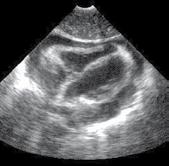

Patternuri de infiltrare a măduvei osoase în MM decelate prin IRM (figura )

Leziunile infiltrative și nodulare întâlnite în MM prezintă hiposemnal T1 datorită absenței grăsimii și cantității crescute de plasmocite din interior; ele prezintă în general un semnal T1 scăzut în comparație cu discurile intervertebrale și musculatura. Pe de altă parte, leziunile prezintă aspect hiperintens pe secvențele T2 FAT SATURATION sau STIR datorită conținutului ridicat de apă și celule, aspect similar altor leziuni osoase maligne[19].

Leziunile MM sunt prezente predominant în scheletul axial și anume vertebre (66%), pelvisul osos (30%) și într-o măsură mai mică la nivelul scheletului extra-axial (coaste, schelet apendicular) [20] În literatură sunt descrise cinci tipuri de infiltrare a măduvei osoase în mielomul multiplu: măduvă cu aspect normal, infiltrare focală a măduvei osoase, infiltrare difuză, infiltrare de tip “sare și piper” și infiltrare combinată focală și difuză [21, 22]; Există o multitudine de studii apărute în literatură care corelează aceste tipuri de infiltrare medulară cu modificările vizualizate la examenele morfo-patologice [23, 24]. În majoritatea cazurilor de MM (28%) se observă un aspect normal al măduvei osoase, cu hipersemnal T1 omogen al acesteia; în cazul infiltrarii, focale se observă diverse leziuni focale T1 hipointense, care pot apărea oriunde la nivelul scheletului; în cazul infiltrării difuze, se observă hiposemnal T1 difuz la nivelul intregii măduve osoase, uneori în caz de infiltrare severă, semnalul fiind chiar mai redus decât cel al discului intervertebral. În doar 3% din cazuri se observă un model de tip „sare și piper” și în 11% din cazuri se poate observa un model mixt de infiltrare nodulară și difuză [22, 25]

Tipuri de afectare medulară în mielomul multiplu: aspect normal imagistic(a), infiltrare focală(b), infiltrare difuză(c) infiltrare de tip ‘sare și piper’, infiltrare mixtă de tip focal și difuz(d). Departamentul de Radiologie al Spitalului Clinic Municipal de Urgență - Timișoara/RO